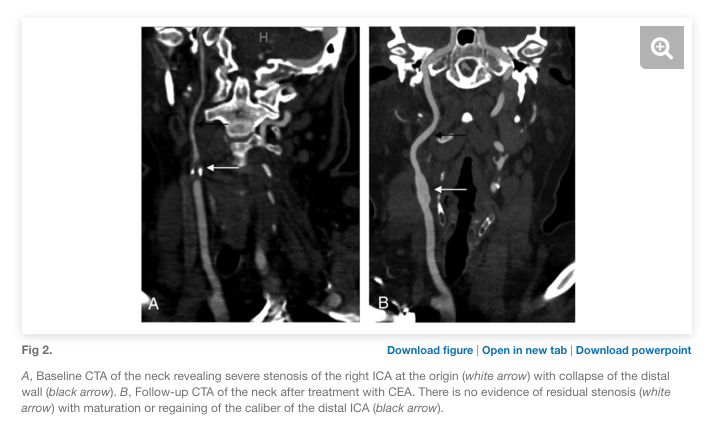

In our series, long-term outcomes showed higher rates of restenosis or asymptomatic interval occlusion than in carotid stenosis without near-occlusion. Still, 79% (stent) and 84% (CEA) had maturation of the revascularized carotid with return of normal vessel caliber.

Back to our patient: they underwent CEA which was complicated by reflex hypotension. This resolved POD #2 and they were discharged home w/o deficits.